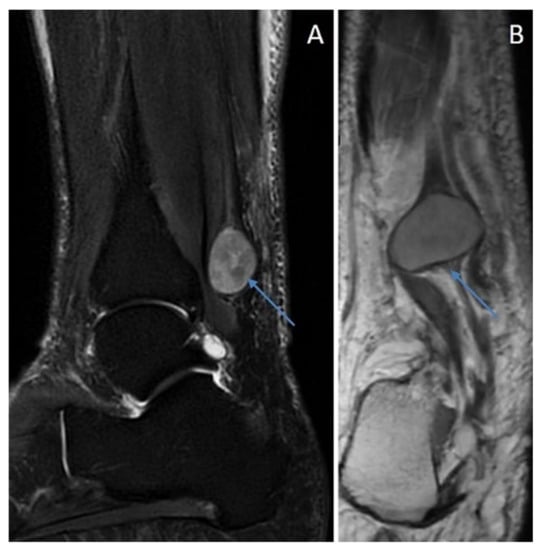

6.4. Plexiform Schwannoma

Immunohistochemical Features